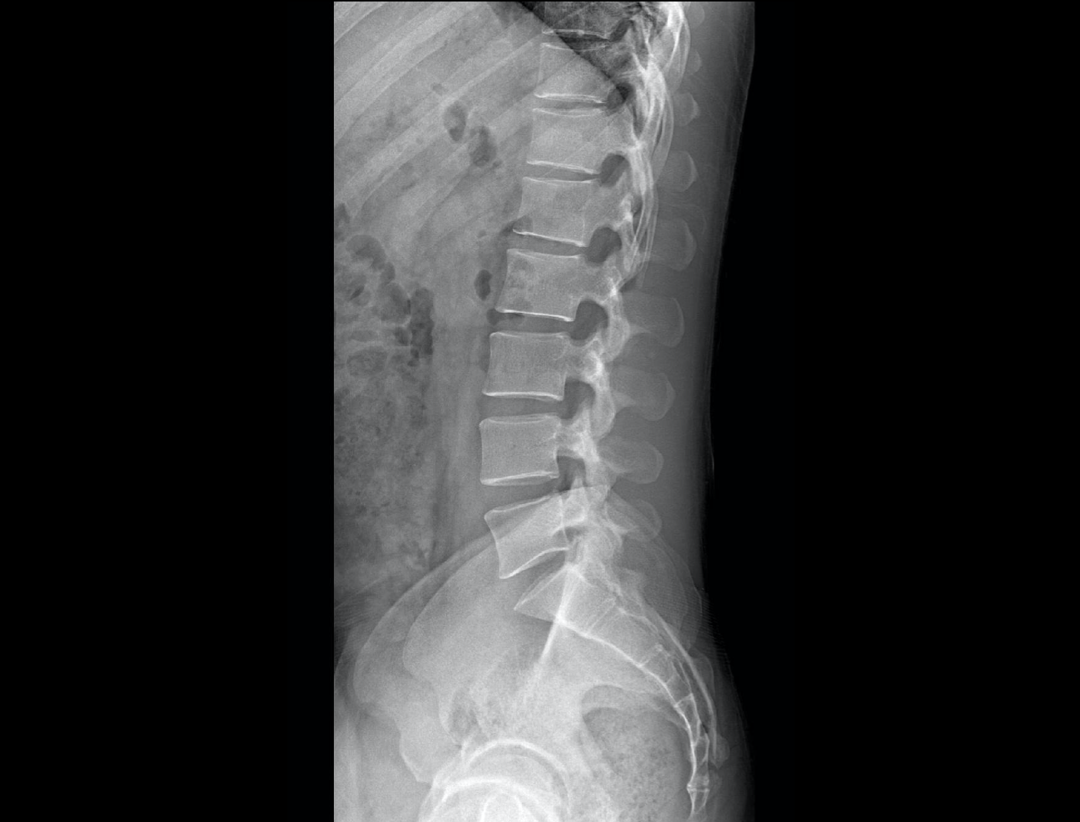

全自动无尺全景拼接

支持自动立位及卧位无尺全景拼接,为骨科、整形外科提供高质量全景影像。

测量功能*

集成脊柱Cobb角及股骨颈干角测量功能,精准指导外科手术及术后评估。

腰椎正位、侧位